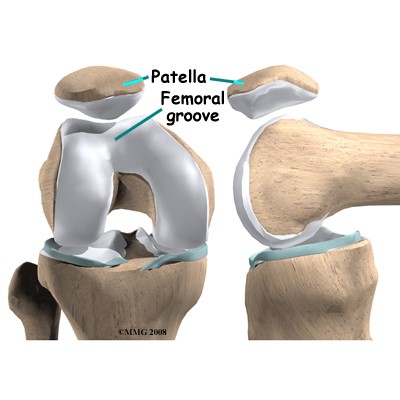

La rodilla es la articulación formado entre tres huesos el fémur, la patela y la tibia. A diferencia de la cadera, la rodilla tiene tres compartimientos funcionales muy definidos: la femorotibial medial (la parte de dentro de la rodilla), la femorotibial lateral (la parte de fuera de la rodilla) y la femoropatelar (la parte anterior de la rodilla). Es una articulación sometido a carga y predispuesto a sufrir desgaste. La artrosis tiene un componente genético y familiar muy importante en su aparición y también en la deformidad presentada por el paciente. La deformidad de piernas más frecuente es la deformidad con las piernas arqueadas hacia dentro (genu varo) en casi 90% de casos. Algunas veces la piernas se deforman hacia fuera (genu valgo). Según la deformidad con la que presenta la rodilla puede afectar un compartimiento, dos o todos cuando la enfermedad es avanzada.

Por tanto, a diferencia de la cadera es posible tratar la artrosis de la rodilla con una gama de protesis según la parte de la rodilla desgastada y la forma de la pierna. Las diferentes protesis para tratar las enfermedades de la rodilla son las prótesis totales cuando toda la rodilla esta gastada y las parciales cuando solo una parte está afectada. La unicompartimental medial es usada para desgaste entre el fémur y tibia por dentro, la unicompartimental lateral cuando el desgaste entre el fémur y tibia es por fuera y la femoropatelar cuando el desgaste es entre el fémur y la patela por delante.

La Prótesis Femoropatelar de Rodilla.

La prótesis parcial femoropatelar de la rodilla es una prótesis especial que está indicado en pacientes con un desgaste muy inicial y con un patrón que afecta solo el compartimiento anterior de la rodilla. Típicamente, son pacientes con dolor en la parte de delante de la rodilla al estar sentados o al subir o bajar escaleras. No les molesta al caminar sobre un terreno plano sin desnivel. Tiene la ventaja de resecar mucho menos hueso del paciente, así preservando más hueso para el futuro. Además, al mantener la parte biológica del cartílago y la ligamentosa de los cruzados de la rodilla, parece conservar mucho mejor la sensibilidad y la marcha de la rodilla (la propiocepción). También la recuperación de esta cirugía (al ser menos agresiva) es más rápida.